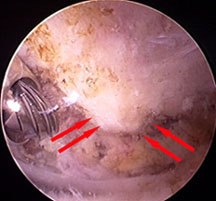

Arthroscopic Picture before Spur Removal

(Electric burr used to remove spur seen on left hand side of picture)